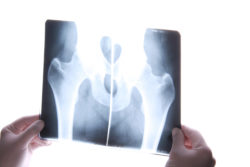

In March 2011, plaintiff John I. was implanted with a DePuy Pinnacle hip replacement device in a total right hip arthroplasty procedure. This DePuy Pinnacle device had a metal acetabular cup liner.

The DePuy Pinnacle device is often fitted with an acetabular cup liner that is made of metal. If this is the case, the metal of the femoral head (the part that fits inside the socket of the acetabular cup) comes into contact with the metal liner of the acetabular cup. This is called a metal-on-metal hip replacement system.

With a metal-on-metal hip replacement system like John’s, there is a risk of DePuy Pinnacle hip complications occurring.